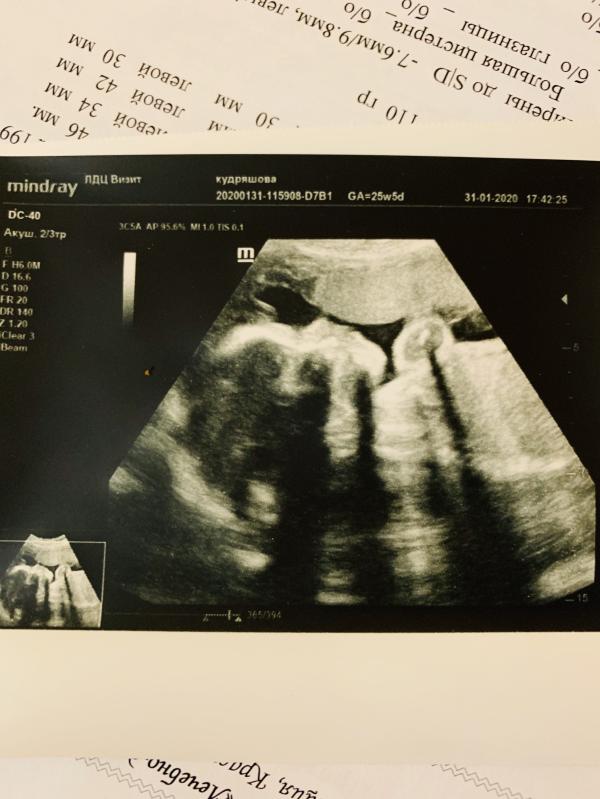

Была я сегодня на узи и осмотре в пц. 😡Инфекция в бак пасёте мазка так и не ушла, 🤦♀️ещё и что то прибавилось из инфекций. До этого была на узи все было хорошо, сейчас у малыша не все в порядке. 😭Узист говорит из за инфекции. Хотя я просила раньше назначить мне антибиотик, как только все вылезло , но врач проигнорировала назначила свечки и ... дождались что теперь наш маленький страдает. В общем сказать что я злая не сказать ничего!!! 🤬А ещё очень страшно за кроху! 😱Может кто сталкивался с таким?? УЗИ добавлю в фото...

Уже, сходила в частную там тоже увидели расширение в боковых желудочков мозга, а вот в сердце сказали ничего не видно плохого...